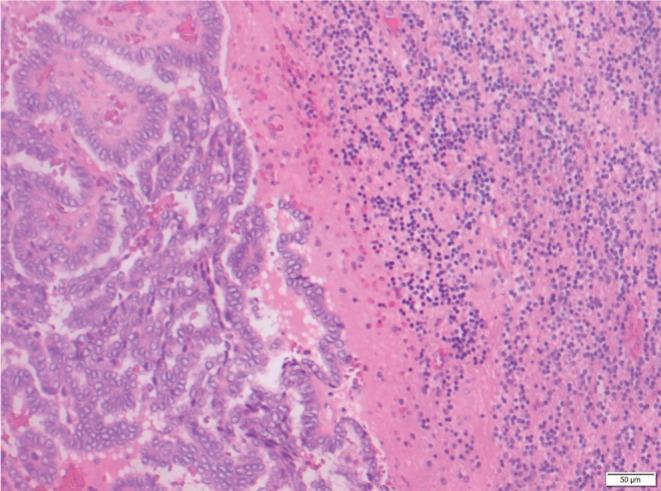

Thyroid cancer is the most common endocrine cancer, with papillary thyroid carcinoma (PTC) accounting for the majority of these cases. Cerebellar metastasis is rarely the presenting feature and confers poor prognosis. Genetic mutations in this setting are most commonly , in contrast to in the majority of PTC. We report the case of an 82 year-old male who presented with a symptomatic right cerebellar lesion and underwent surgical resection to demonstrate metastatic PTC. Extensive workup with computed tomography, neck ultrasound and FDG-PET was suggestive of a left thyroid primary lesion, with FNA confirming PTC. However, total thyroidectomy demonstrated incidental microMTC (medullary thyroid microcarcinoma, defined as tumour <10mm) without any evidence of PTC, whereas the left level VI neck dissection demonstrated a 30mm nodule of PTC without identifiable normal thyroid or lymph node tissue.

甲状腺癌是最常见的内分泌癌,其中甲状腺乳头状癌(PTC)占大多数病例。小脑转移很少是首发特征,且预后较差。与大多数PTC不同,这种情况下的基因突变最常见的是 。我们报告了一例82岁男性病例,该患者出现有症状的右侧小脑病变,并接受了手术切除,结果显示为转移性PTC。通过计算机断层扫描、颈部超声和氟脱氧葡萄糖正电子发射断层扫描进行的全面检查提示左侧甲状腺有原发性病变,细针穿刺活检证实为PTC。然而,甲状腺全切术显示意外发现微小髓样甲状腺癌(髓样甲状腺微癌,定义为肿瘤<10mm),未发现任何PTC证据,而左侧VI区颈部淋巴结清扫显示一个30mm的PTC结节,未发现正常甲状腺或淋巴结组织。